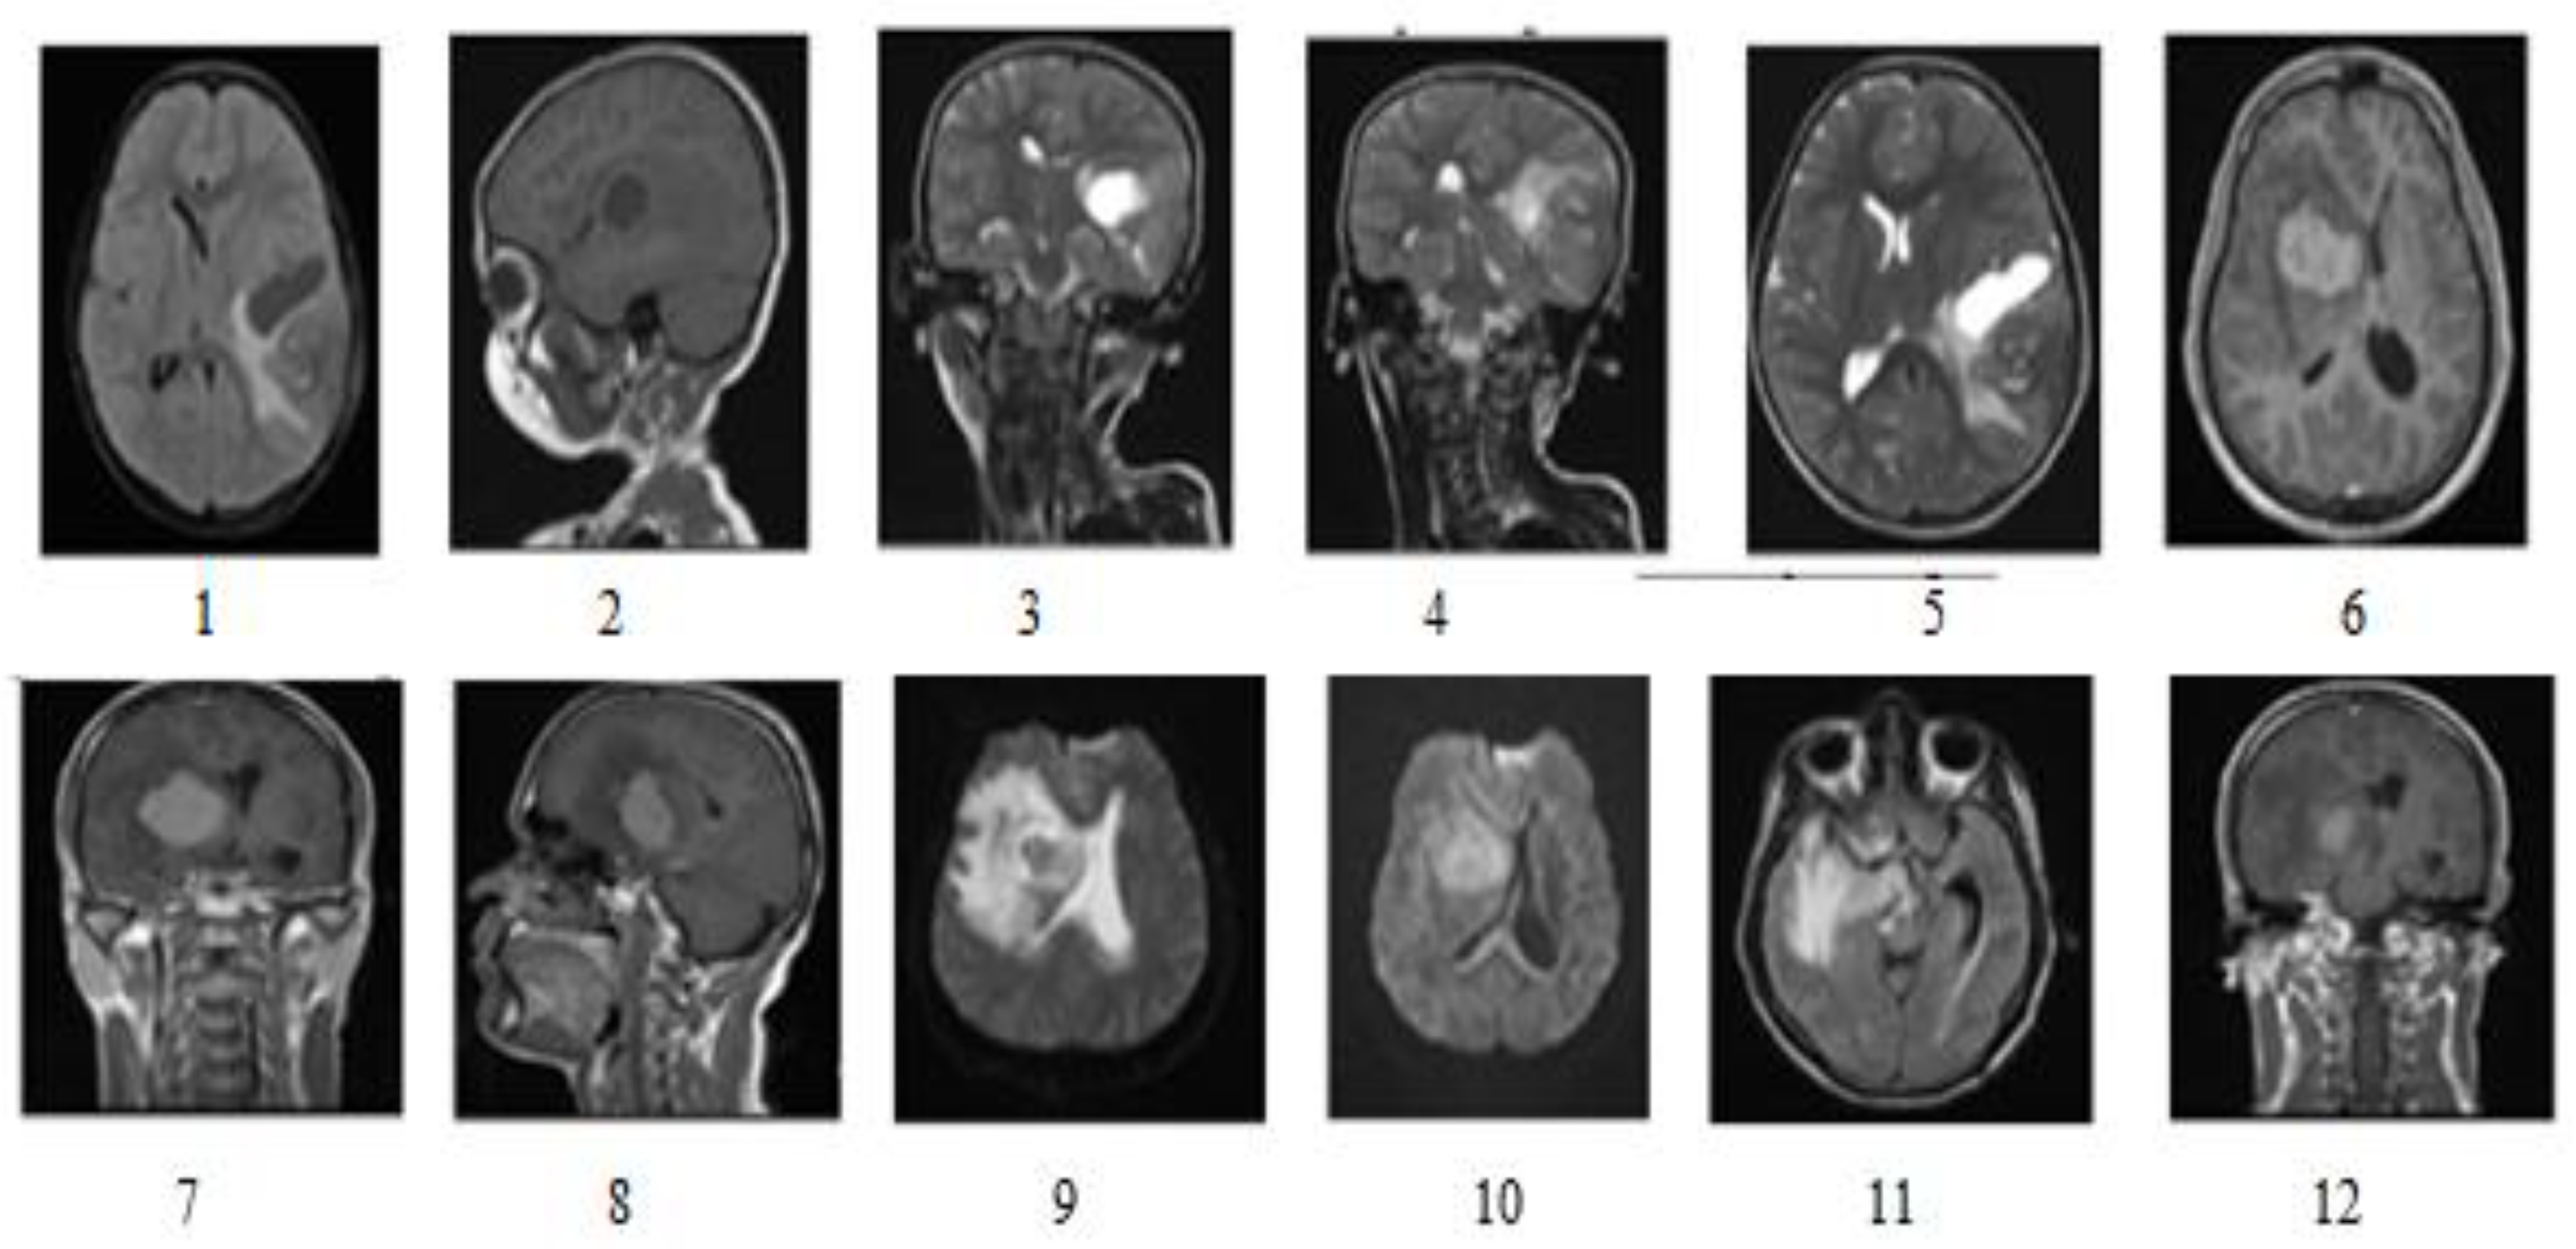

3.1. Dataset

3.2. Proposed Method

3.2.1. Pre-Processing